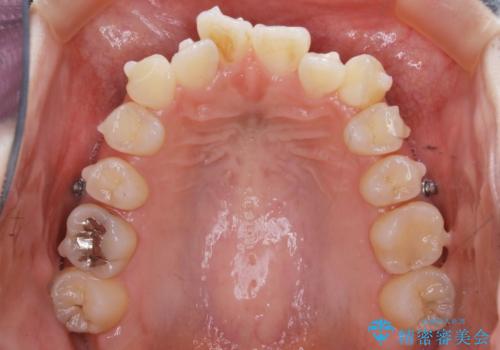

矯正装置の希望がインビザラインだったため、マイクロインプラントを併用し、奥歯から順に遠心移動をかけていくことにより非抜歯でも主訴のガタつきを治すことができました。

マウスピースとマイクロインプラントを組み合わせることで、抜歯をしなくても歯並びを治すためのスペースを作ることができます。奥歯から順に移動させていくので前歯に変化が出るまでには時間がかかりますが、その分健康な歯を抜歯することなく理想的な歯並びを手に入れることができます。